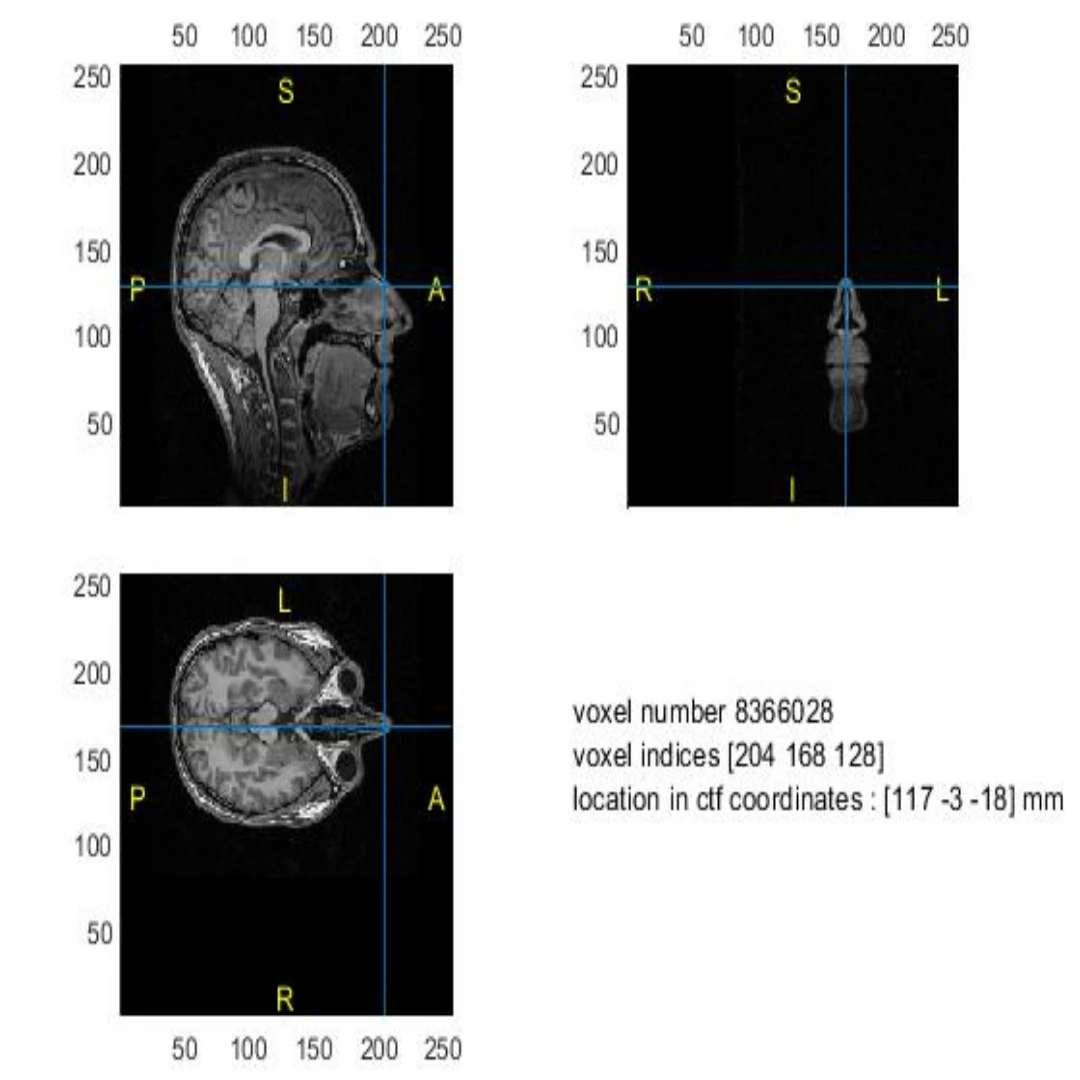

در این تمرین هدف اصلی آشنایی با نحوه ساخت مدل سر (Head Model) با استفاده از داده‌های MRI و روش‌های مختلف سگمنتیشن شامل BEM و FEM و همچنین تحلیل تفاوت‌های آن‌ها در فرآیند پردازش سیگنال EEG می‌باشد.